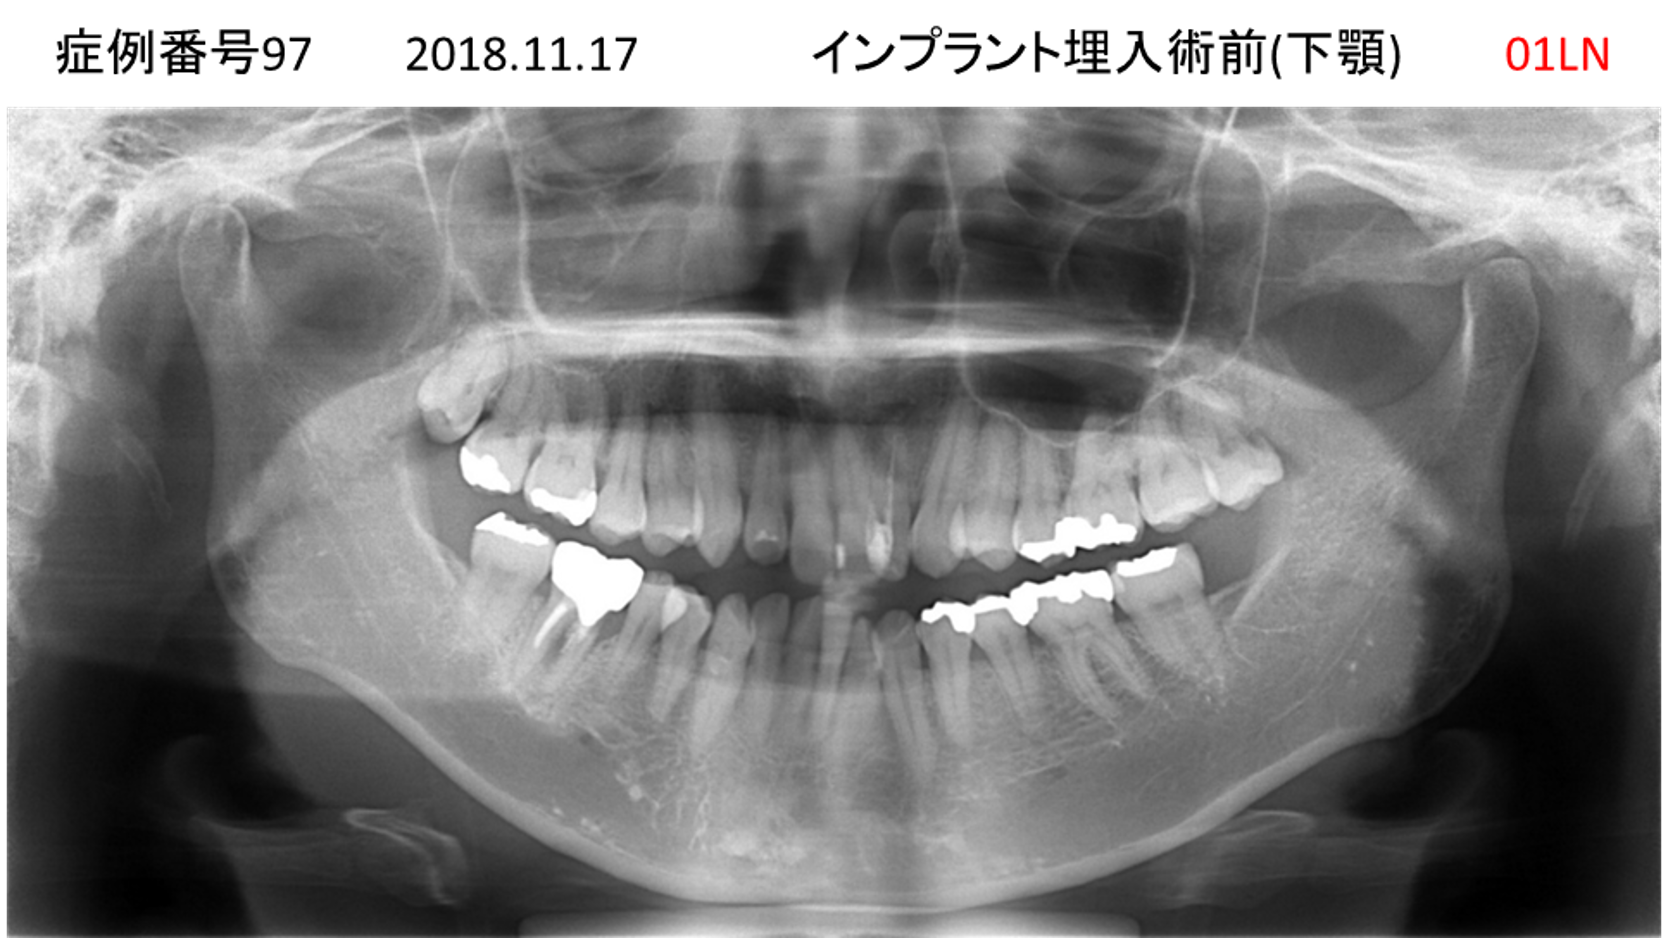

全く噛めない患者様のインプラント症例

| 治療名称 |

インプラントAGC |

| 治療費用 |

860万円+税 |

| 治療期間 |

12か月 |

| 患者さんの症状(主訴) |

全く噛めない、ごはんが後もに食べられるようになりたい、人前で口元を隠したくない |

| 治療内容 |

サイナスリフト、GBR、インプラント、AGC |

| 治療結果 |

しっかり噛めて踏ん張ることができる。食べ物をを選ばなくて済む、何でも食べられる、体重が増えた。見栄えがきれいすぎて自分じゃないみたい |

| 治療の注意点(リスク/副作用) |

インプラントが壊れたら再治療が必要 |